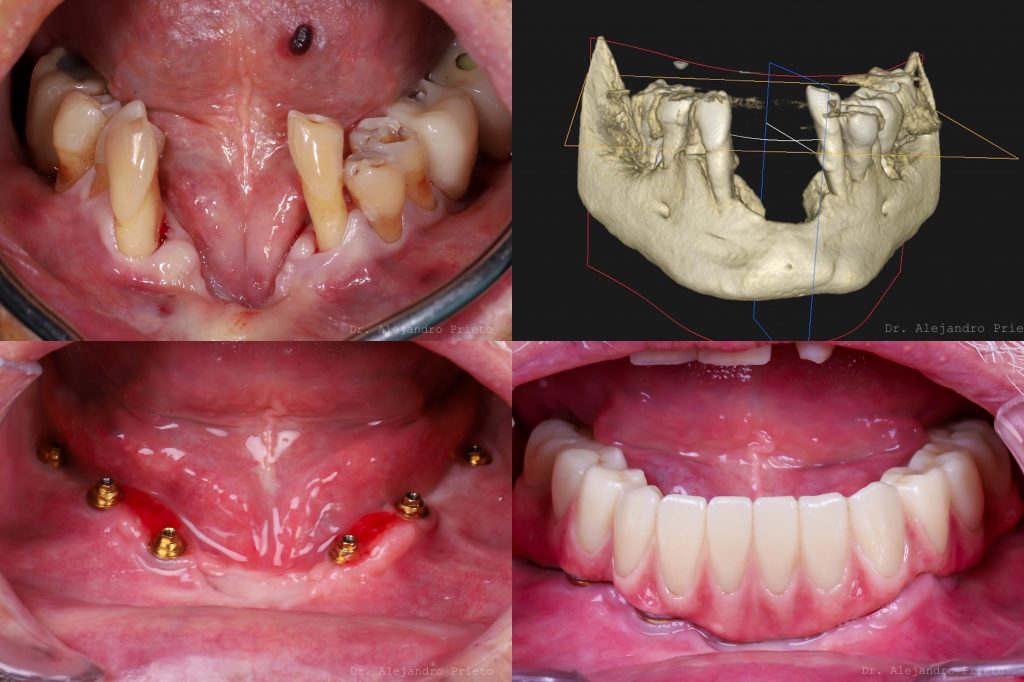

El injerto de hueso dental es un procedimiento de regeneración ósea avanzada que permite recuperar el volumen óseo perdido para colocar implantes dentales con seguridad. En Alejandro Prieto Dental, en Madrid, utilizamos planificación digital 3D y biomateriales de alta calidad para regenerar hueso incluso en casos complejos. Es un tratamiento indicado cuando el hueso no tiene suficiente altura o anchura, algo frecuente en pacientes que han perdido piezas dentales hace mucho tiempo o que han sufrido periodontitis avanzada.

El injerto consiste en añadir y estimular la formación de hueso nuevo en zonas donde se ha reabsorbido. Muchos pacientes preguntan si el hueso dental se regenera solo, o cómo regenerar hueso dental naturalmente. Aunque ciertos hábitos y vitaminas para regenerar hueso dental pueden ayudar a mantener la salud ósea, no pueden sustituir un injerto cuando el hueso ya se ha perdido. En estos casos tampoco existe un medicamento para regenerar hueso que lo solucione por sí solo. Cuando el volumen es insuficiente, el injerto es una de las mejores opciones para poder colocar implantes.

En función del defecto óseo se elige entre injerto en bloque, cirugía ósea guiada, elevación de seno, expansión ósea. O incluso el uso de implantes especiales para pacientes sin hueso.

3. Cirugía del injerto

El procedimiento se realiza bajo anestesia local o sedación. El injerto se coloca en la zona a regenerar y se estabiliza mediante membranas o fijaciones, según cada caso.

• Casos avanzados donde no se puede regenerar hueso dental sin recurrir a técnicas quirúrgicas más complejas, como injertos en bloque múltiples o injertos microvascularizados. En este caso, hay que recurrir a implantes especializados como implantes cigomáticos o implantes sin tornillos.